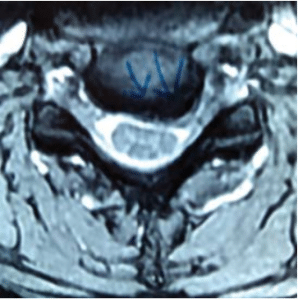

MRI showed severe prolapsed cervical disc indenting the spinal cord and neuroforamen’s of C5/6. There was evidence of spinal cord pressure with T2 changes seen on the sagittal views.